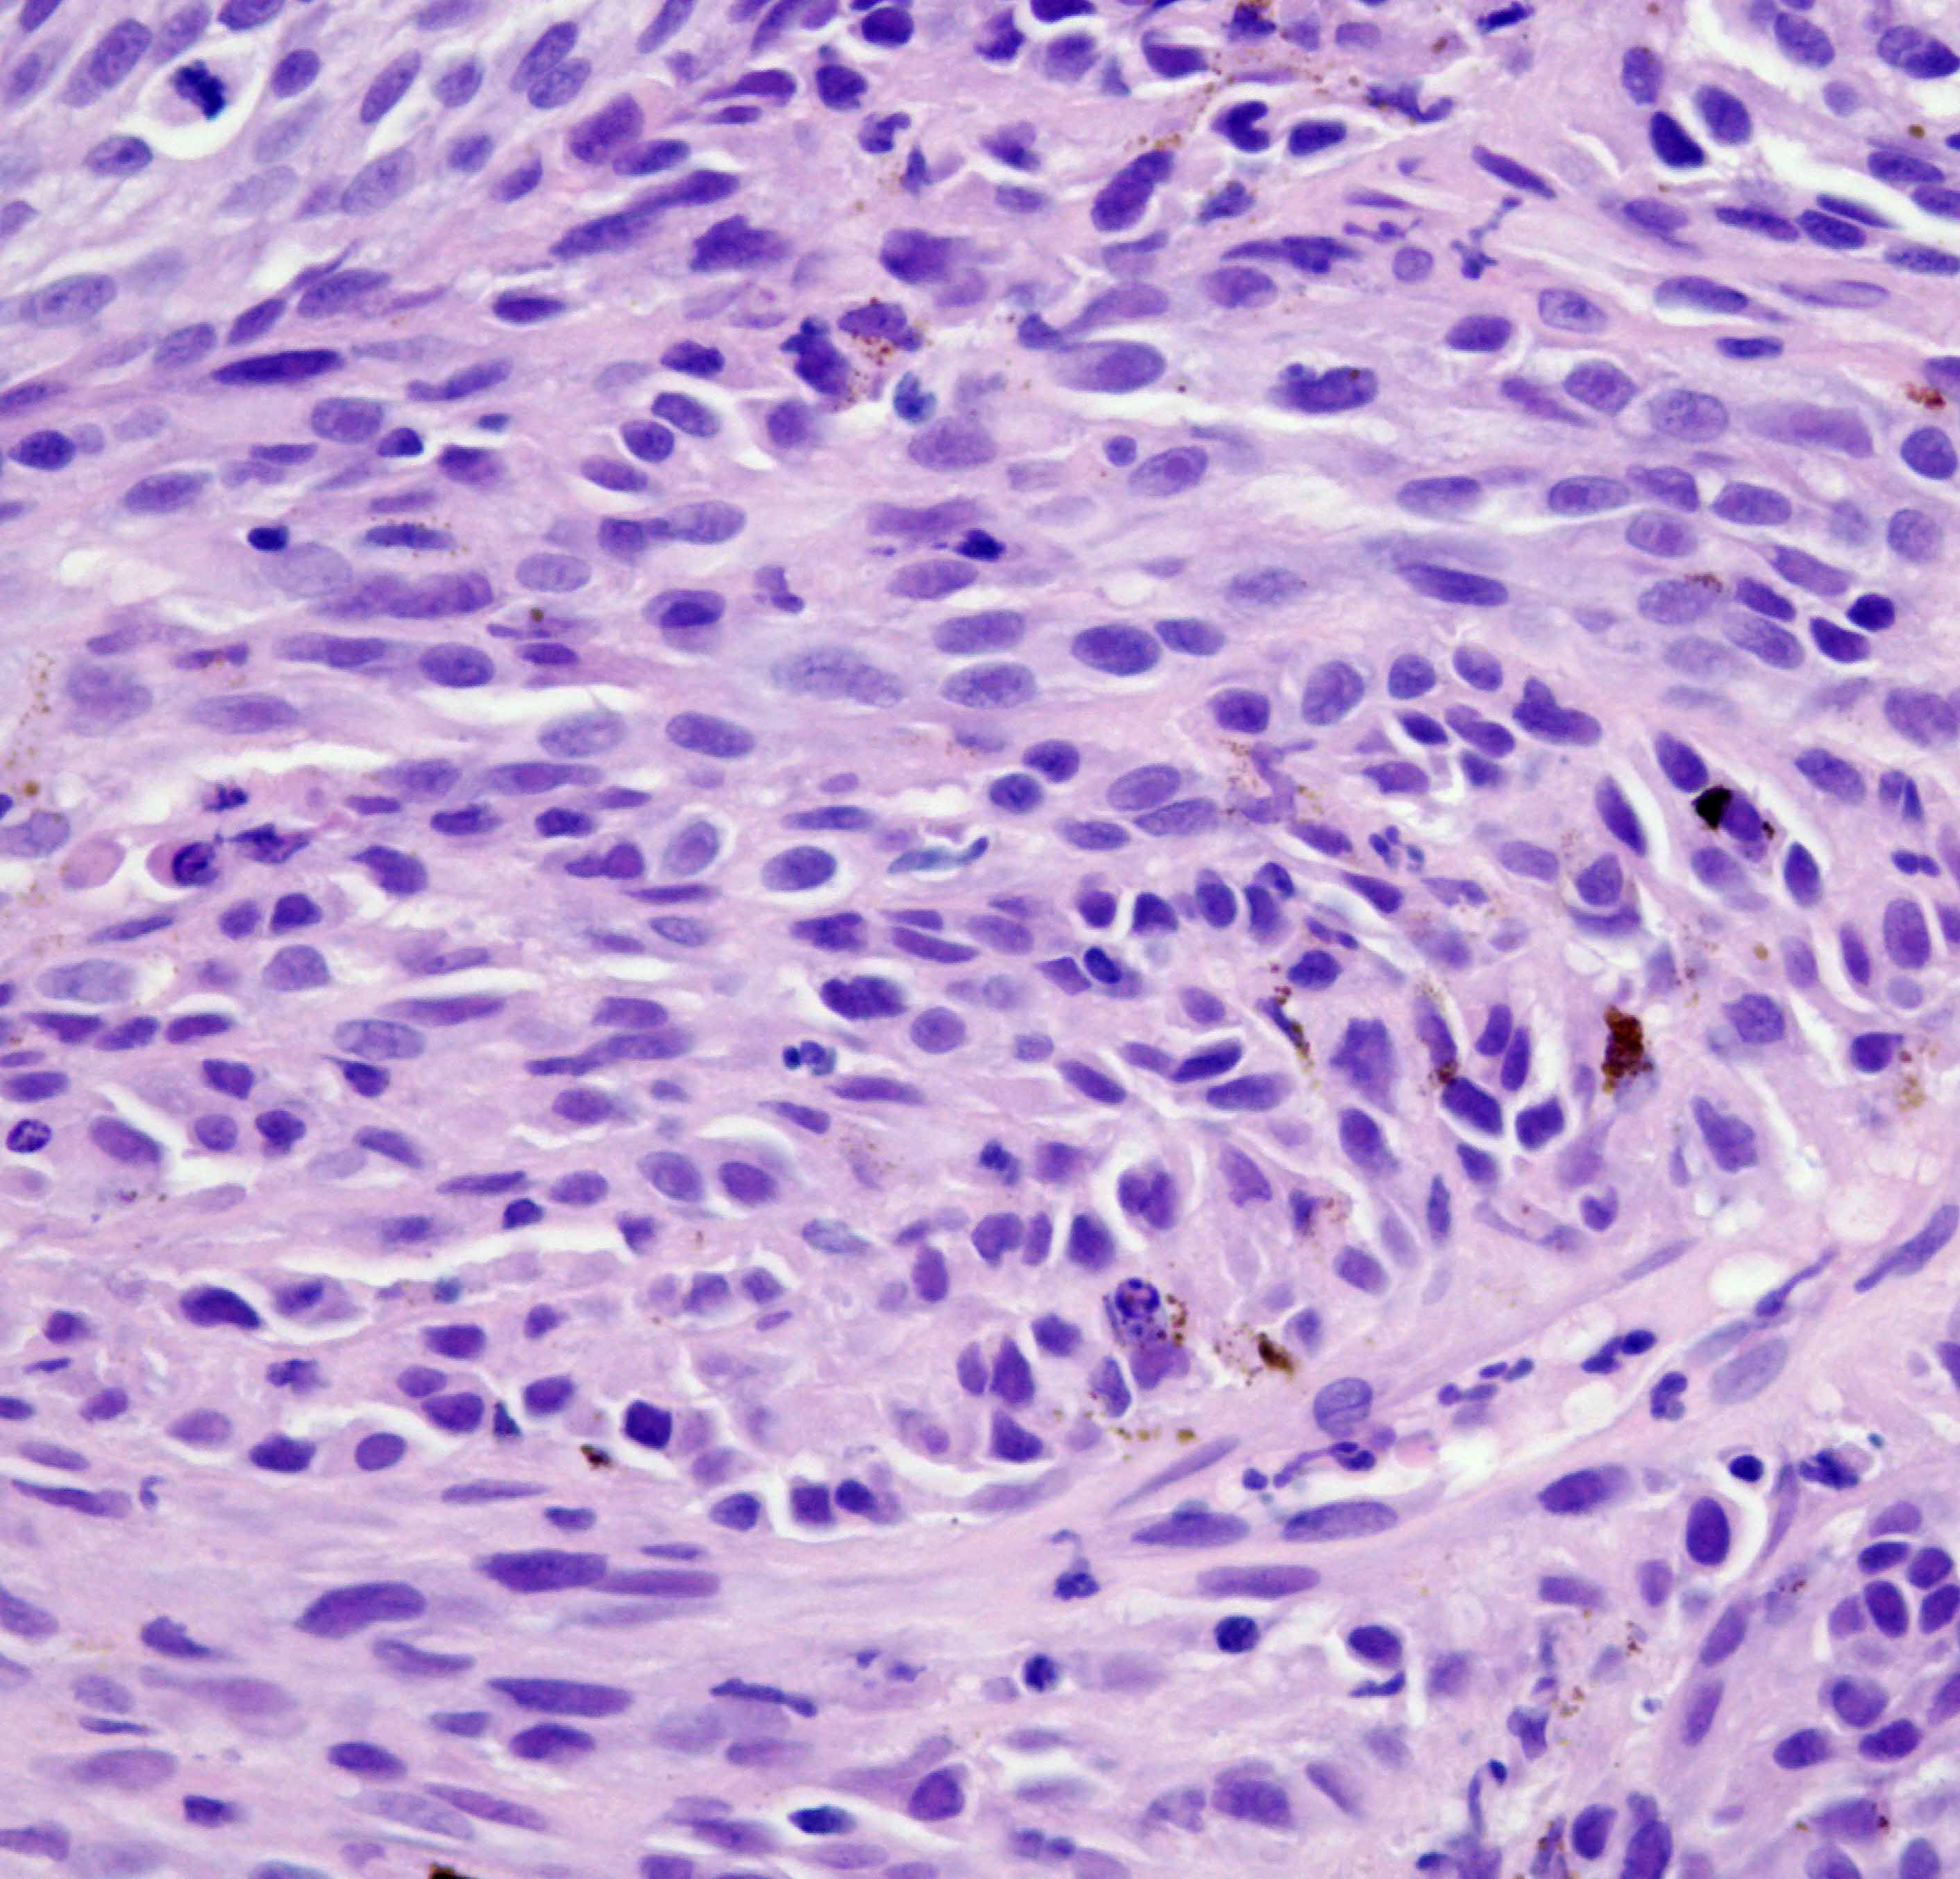

Histopathology of the nose mass: Pleomorphic population of variably shaped neoplastic cells arranged in nests and whirls with occasional brown pigment granules in cytoplasm, marked anisocytosis and anisokaryosis, and frequent mitotic figures. Findings are consistent with a malignant neoplasm.